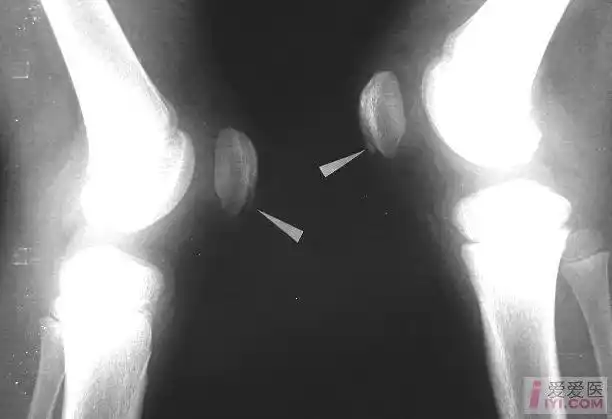

二分髌骨.jpg